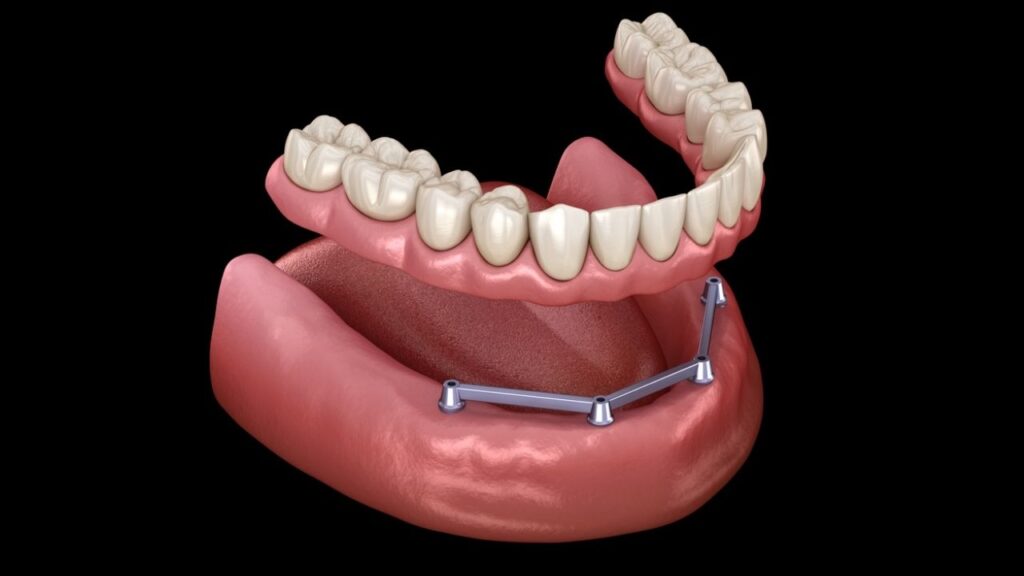

Overdenture

Overdenture, Dentadura Grampeada ou Sobredentadura, nada mais é do que uma Dentadura convencional (Removível) grampeada à implantes. Essa modalidade de prótese pode ser utilizada como temporária, provisoriamente, ou mesmo definitiva. Usualmente requerem menor quantidade de Implantes: Inferior 2 e superior 2 a 4 . Existem vários sistemas de grampeamento:  Ouring; Barra clip e até sistemas imantados. Cabendo ao Implantodontista a melhor escolha.